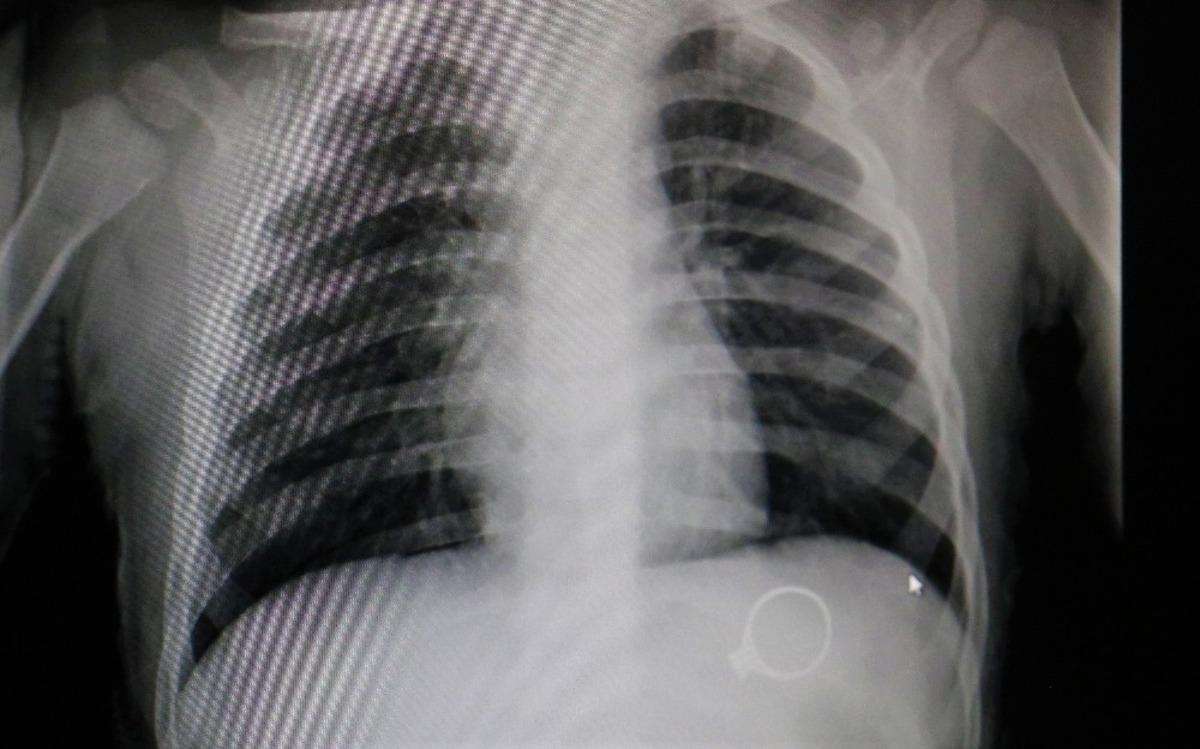

Sivas’ta kent merkezinde yaşayan F.G. ve C.G. çiftinin 1.5 yaşlarındaki M.G adındaki bebekleri oynamak için annesinden tek taş yüzüğünü istedi. Yüzükle oynayan M.G. annesine fark ettirmeden yüzüğü yuttu. Bir süre sonra çocuğunun yüzüğü yuttuğunu fark eden anne çocuğunu kucaklayarak Sivas Medicana Hastanesine götürdü. Burada Çocuk Cerrahisi Uzmanı Op.Dr. Mahmut Aluç tarafından muayene edildi. Yüzüğün, röntgeni çekilen M.G’nin midesinde olduğu görüldü. 6 gün sonra yüzük doğal yollarla çıktı. Çıkan yüzük aileye rahat bir nefes aldırdı.

RÖNTGENDE BELLİ OLDU

Çocuk Cerrahisi Uzmanı Op.Dr. Mahmut Aluç, çekilen röntgende yüzüğün midede olduğunu belirlediklerini ifade ederek, “Hastamız 1 buçuk yaşında. Bundan 6 gün önce bize yüzük yutma şikayeti ile başvurdu. İlk çektiğimiz grafide yüzüğün mide de olduğunu saptadık ve aileyi bilgilendirdikten sonra rutin prosedürlerinin gereği beklemeye başladık. 6 gün sonra spontane olarak yüzüğün kendisi çıktı. Bu tür hastalarla oldukça sık karşılaşıyoruz. Rutin olarak şöyle bir kural vardır, çocuk ağzına aldığı her şeyi yutabilir. Özellikle küçük çocuklar cisimleri tanımak için elleriyle dokunduktan sonra genellikle ağızlarına alırlar. Bu yutulan cisimler toplu iğne olabilir, çengelli iğne olabilir, para olabilir” dedi.